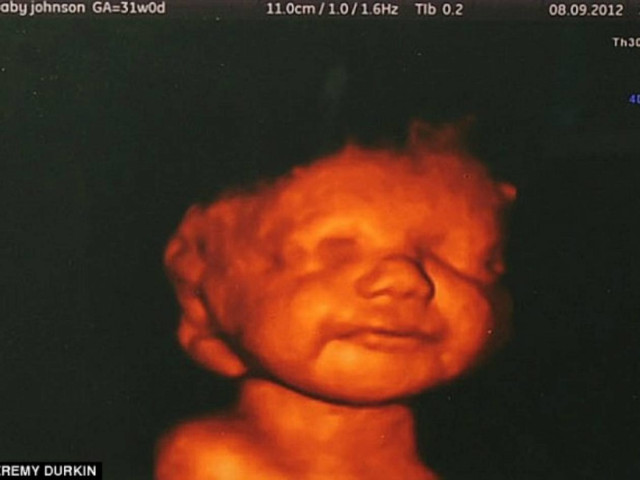

Το χαμόγελο του αγέννητου μωρού της, την έκανε να αλλάξει γνώμη.

Η συμβουλή των γιατρών ήταν να κάνει έκτρωση όμως ένα χαμόγελο της άλλαξε γνώμη. Ήταν το χαμόγελο του αγέννητου μωρού της στο τρισδιάστατο υπερηχογράφημα. Mπόρεσε να δει πεντακάθαρα το μωρό της να χαμογελά, να κλωτσά και να κουνά τα χεράκια του, με αποτέλεσμα να συγκινηθεί τόσο ώστε να μην μπορέσει να προχωρήσει στην έκτρωση όπως αναφέρει η Daily Mail.